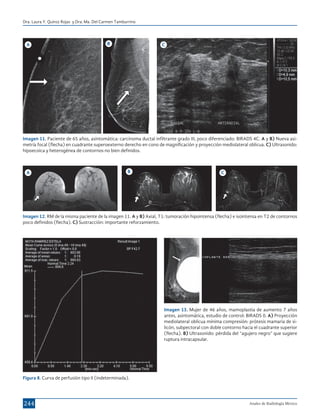

Imagen 11. Paciente de 65 años, asintomática: carcinoma ductal infiltrante grado III, poco diferenciado: BIRADS 4C. A y B) Nueva asimetría focal (flecha) en cuadrante superoexterno derecho en cono de magnificación y proyección mediolateral oblicua. C) Ultrasonido:

Imagen 12. RM de la misma paciente de la imagen 11. A y B) Axial, T1: tumoración hipointensa (flecha) e isointensa en T2 de contornos

Imagen 13. Mujer de 46 años, mamoplastia de aumento 7 años

(flecha). B) Ultrasonido: pérdida del “agujero negro” que sugiere